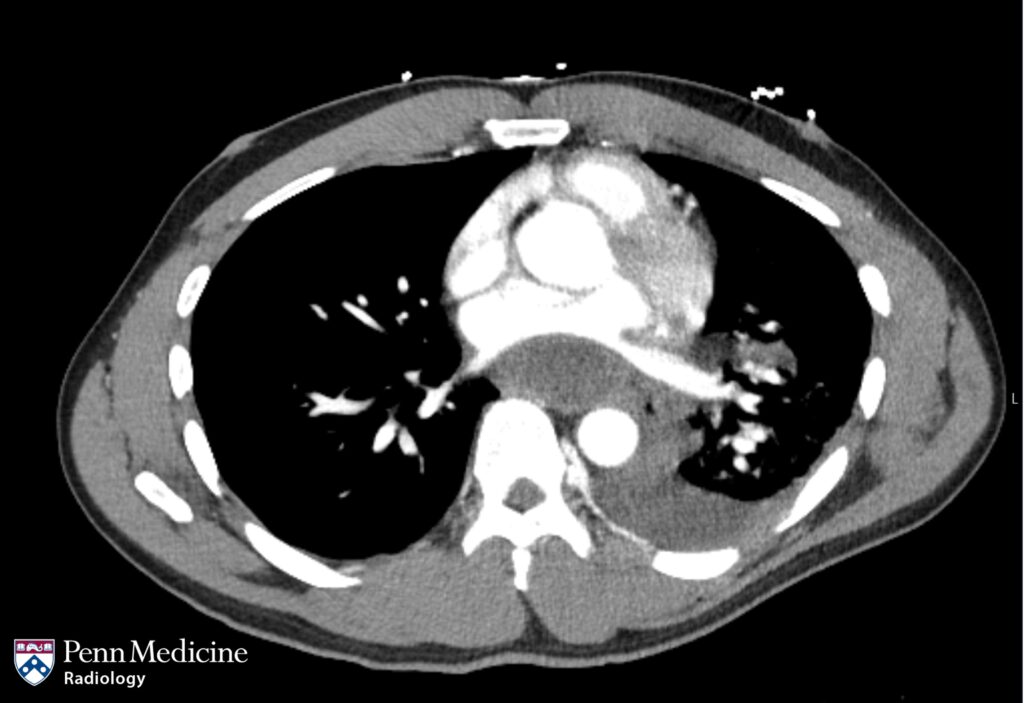

A 60-year-old woman with a history of stage IA invasive ductal cell carcinoma of the left breast (postlumpectomy and postradiation) and Roux-en-Y gast…